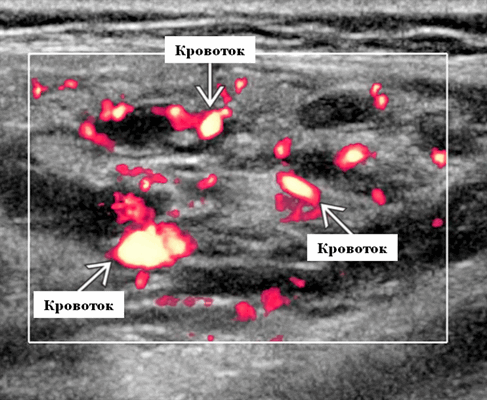

Ультразвуковая визуализация слюнной железы. Общие особенности

Лучший диагностический критерий. Неоднородно гипоэхогенное поражение, синусоидальные сосудистые пространства, движение вперед и назад в реальном времени ± эхогенные флеболиты. Выраженный сигнал потока на цветном или энергетическом доплеровском режиме. Монофазный низкоскоростной поток на импульсном доплеровском режиме

Результаты ультразвукового исследования. УЗИ в серошкальном режиме. Большинство сосудистых венозных гемангиом (80%) выглядят неоднородно гипоэхогенными. Большие анэхогенные сосудистые пространства видны менее чем в 50% случаев, серпигинозные и синусоидальные. Поражения с небольшими сосудистыми каналами могут казаться эхогенными (из-за множества акустических границ, отражающих звук). Определить пределы образования бывает трудно, так как компоненты поражения могут быть изоэхогенными в околоушной паренхиме и незаметно смешиваться. Внутрипросветное движение эхо-сигналов при УЗИ в реальном времени, представляющее медленный сосудистый кровоток. Характерны эхогенные флеболиты с задним акустическим затенением. Сообщается, что они присутствуют только в 20% ВСМ. Иногда поражается вся околоушная железа, имитируя диффузную или инфильтративную патологию. Целесообразность склеротерапии оценивается соотношением сосудистых пространств к эхогенной матрице

Импульсный допплер. Монофазный, низкоскоростной поток может иногда обнаруживаться в анэхогенных и гипоэхогенных пространствах, представляющих открытые сосуды со значительным кровотоком. Отсутствие допплеровского сигнала при медленном кровотоке или тромбировании

Цветной допплер. Выраженный цветной доплеровский сигнал присутствует в областях, где поток значительный. Используйте фильтр для стенок сосудов и низкую частоту повторения импульсов (PRF) для увеличения доплеровской чувствительности. Отсутствует допплеровский сигнал при медленном кровотоке или тромбировании. Доплеровский сигнал потока изменяется различными маневрами. В поверхностных участках доплеровский сигнал может быть остановлен прямым сжатием датчика над поражением. Сигнал потока может иногда быть усилен маневром Вальсальвы или дистальным сжатием, но последнее трудно выполнить в области лица.